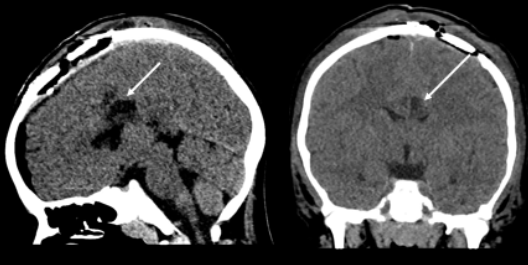

在细致的术中操作下,鲁特卡教授最终成功且安全地切除肿瘤。

术后,小洛并未出现任何新发神经功能损伤,在随访的2年时间内,他的癫痫也并未发作。术后的病理结果证实,引发癫痫的正是节细胞胶质瘤。